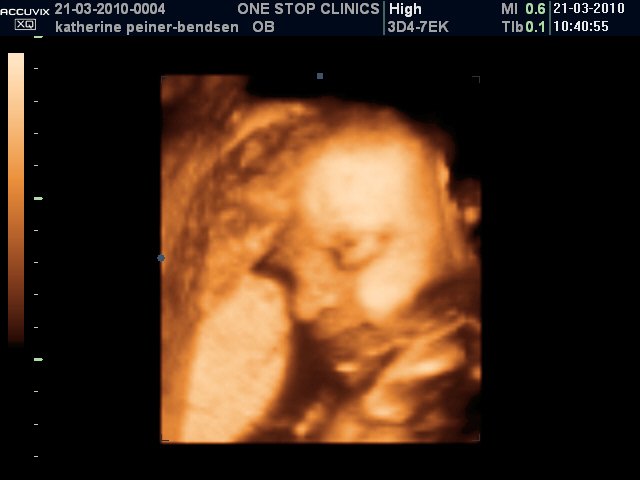

Bb3031

Scanningsbilleder af Alexander taget i uge 31.

Han puttede sig godt ind mod moderkagen med sin højere side af ansigtet, så vi fik desværre aldrig et fuldt profilbillede af den lille gut  Men tilgengæld oplevede vi, at han åbnede sine øjne en del gange og blinkede til os

Vedhæftede fotos (klik for at se i fuld størrelse)